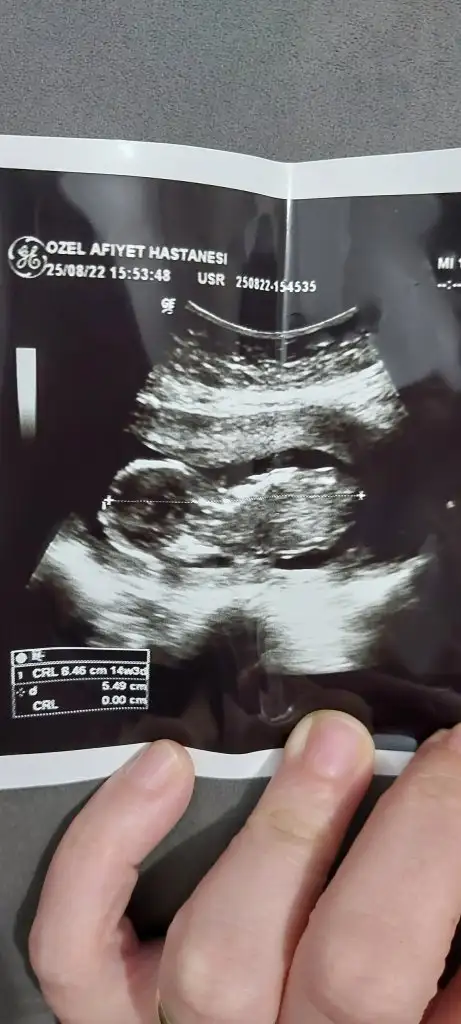

Karından utrason fotosu ayrıca 14 haftalikSelamm ilk görüyorum siziıi

Meraktan çatlıyorum bana da bakar mısınız rica etsem